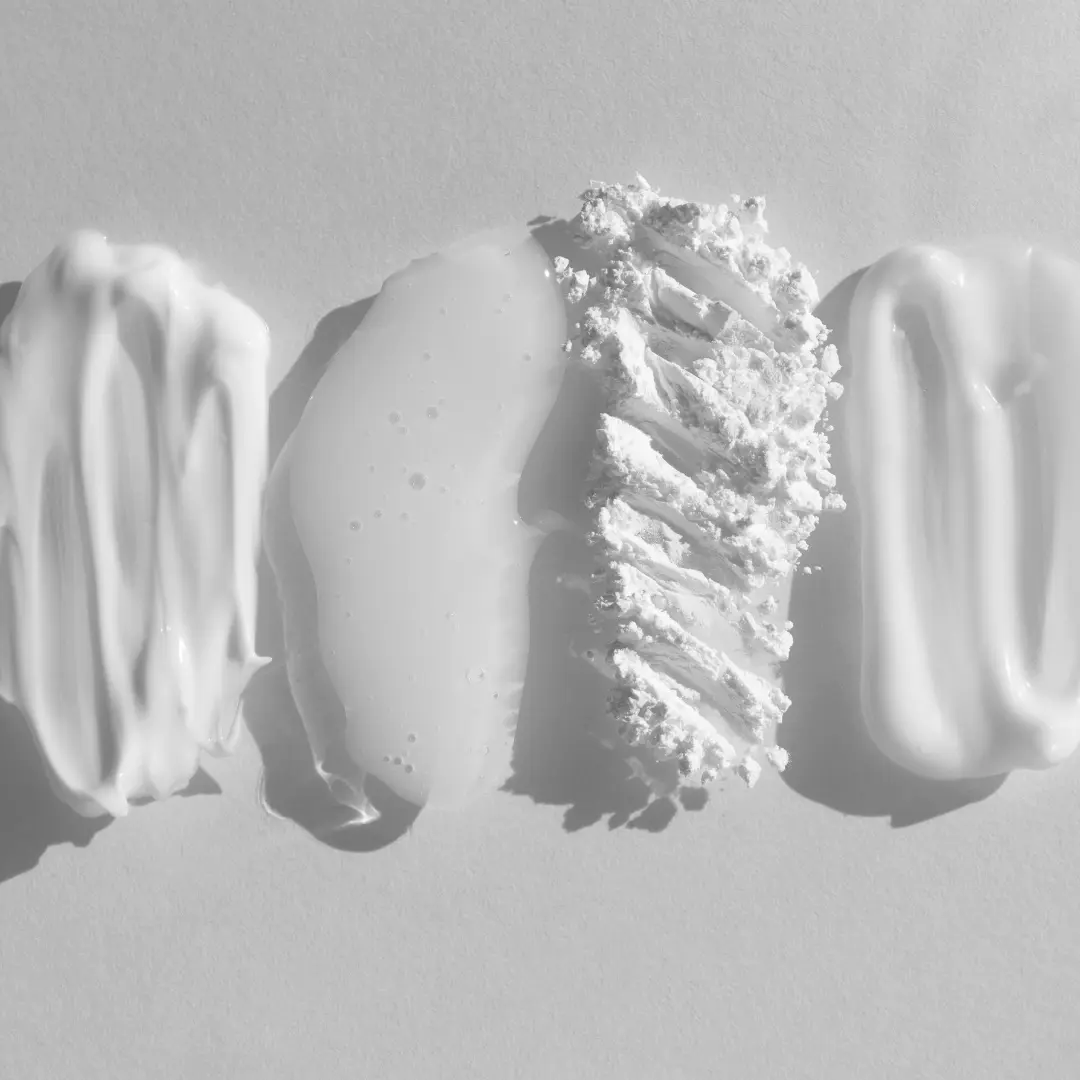

Existen varias estrategias de hidratación en la dermatitis atópica, basadas en la capacidad de la crema para restaurar la barrera cutánea y mejorar la estructura de la piel. Las cremas para la dermatitis atópica están diseñadas para imitar los componentes naturales de la piel y ayudar a retener la humedad, evitando la pérdida transepidérmica de agua.

1. Cremas con glicerol

2. Cremas con petrolato

3. Cremas con ceramidas

6. Cremas de nueva generación para eccema leve